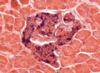

Pineal gland - pinealocytes, interstitial cells, brain sand

Pineal gland: made of nervous tissue, nuclei belong to one of 2 cell types. Larger nuclei that stain lighter belong to pinealocytes (make melatonin). Darker, elongated nuclei are interstitial cells. Brain sand (aggregates of calcified secretions and calcified ECM)

Pineal gland: pinealocytes, brain sand ( corpora arenacea )

Pinealocytes of pineal gland